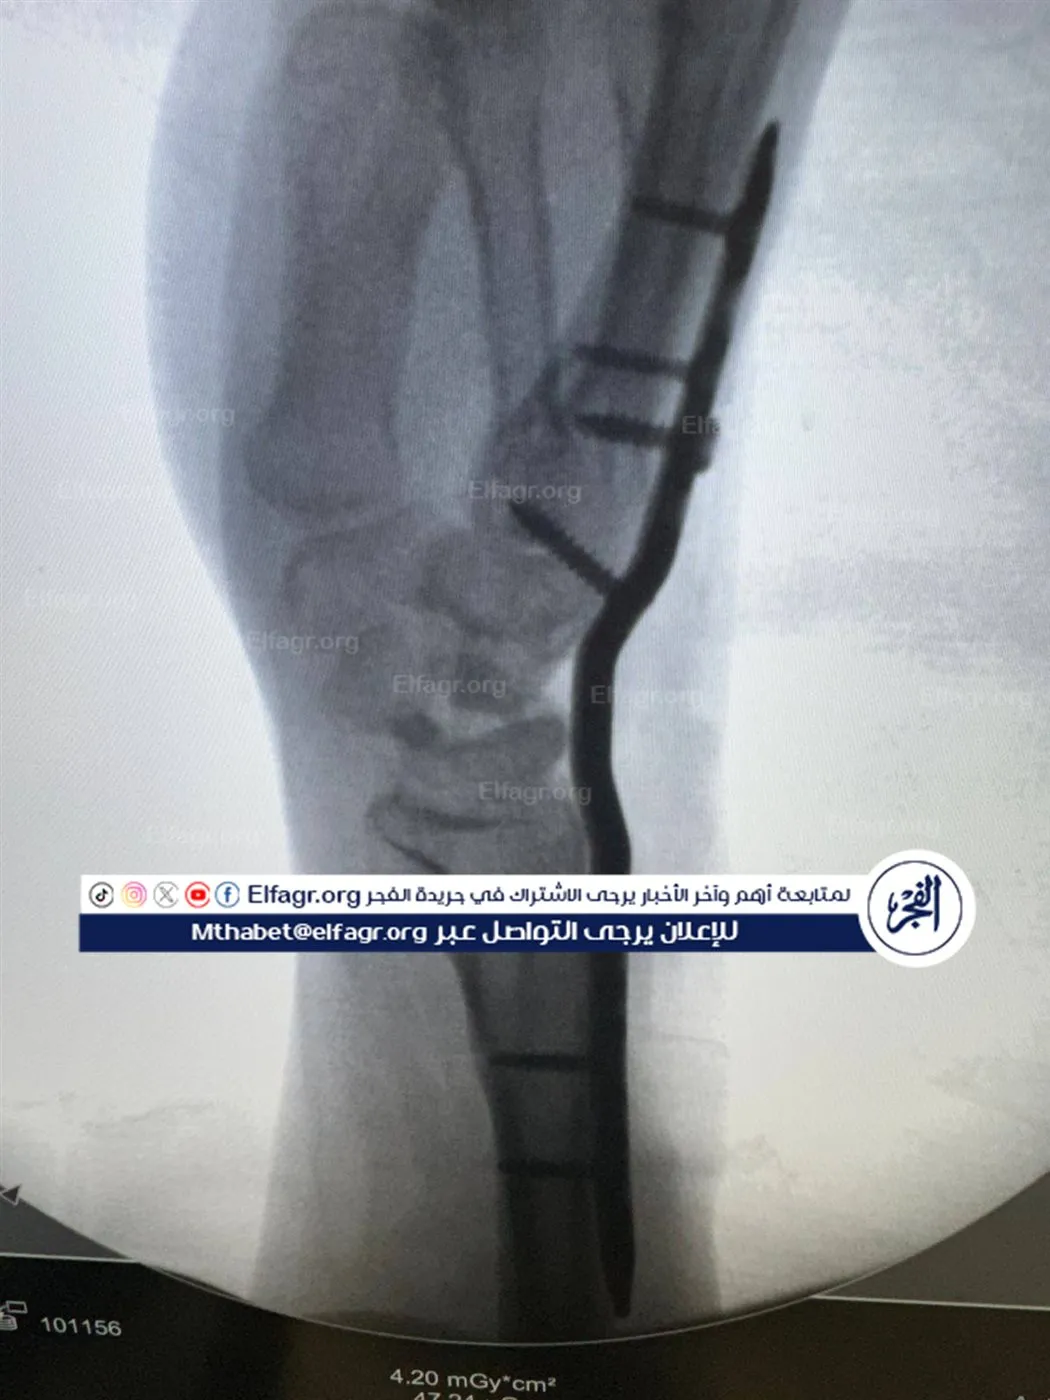

يشير فارس إلى أنه كان متفقًا مع النادي على إجراء العملية باستخدام المنظار، إلا أنه فوجئ بإجرائها جراحيًا في أحد المستشفيات بالقاهرة بتاريخ 5 فبراير 2024، قائلا: اتفقت معاهم إنها هتتعامل بالمنظار، لكن لقيتها اتعملت جراحة مفتوحة.. قالوا لي هتبقى زي الفل، لكن بعد ما فكت الجبس اكتشفت إن إيدي محتاجة عمليات تانية.

ويؤكد اللاعب أنه خضع لاحقًا لعمليتين إضافيتين على نفقته الخاصة، بعدما تدهورت حالته وأصيب بعجز في حركة اليد، قائلا: مبقاش في أي حركة وحياتي الكروية انتهت، وتصاعد الأزمة تصاعدت عندما عاد إلى النادي لمتابعة حالته، ليُفاجأ بقرار فسخ التعاقد دون إخطاره رسميًا، قائلا: العقد بتاعي ساري لحد 2027، ومفيهوش بند يسمح بفسخه من طرف واحد وفجأة قالوا لي ملكش حاجة عندنا، كما أكد أن النادي لم يقم بتحرير وثيقة تأمين خاصة بإصابته، رغم كونها إصابة عمل حدثت أثناء التدريب.